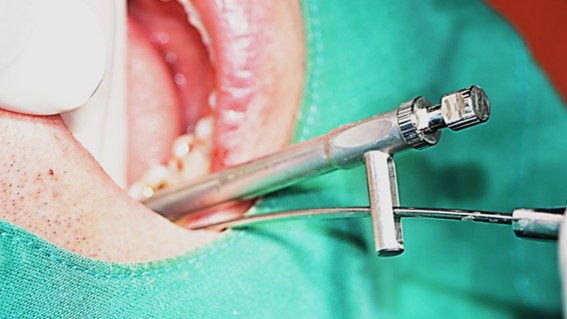

▲Arum Dentistry NB1 5*10